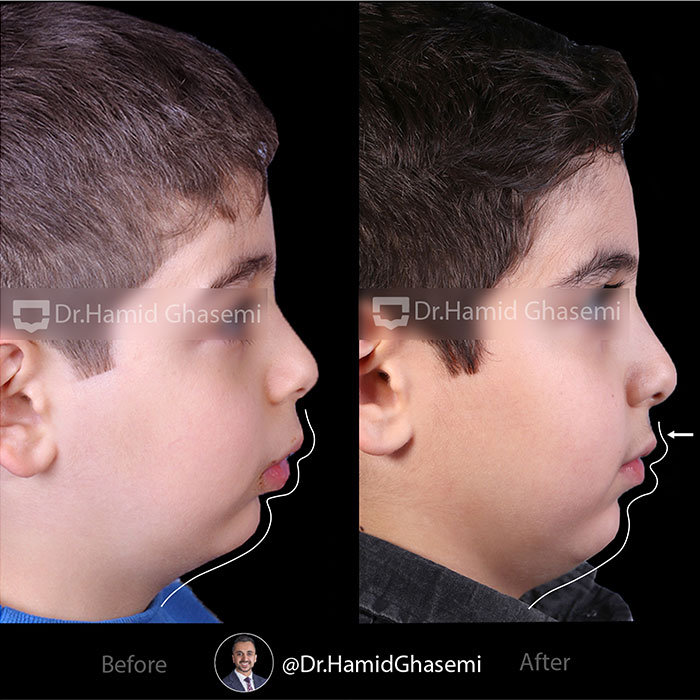

شماره پرونده: 96-1448

دیستالیزیشن (عقب بردن) فک بالا در پسر ۱۰ ساله با فک بالای جلو زده با استفاده از دستگاه هدگیر و درمان ثابت 2×4 جهت مرتب کردن دندانهای قدامی. به تغییرات حالت لب بالا بعد از دیستالیزیشن فک بالا دقت کنید.

Upper arch distalization in 10 years old boy with prognathic maxilla using headgear and 2×4 fixed braces to level and align front teeth. Attend to the upper lip posture after upper arch distalization

دکتر قاسمی بهترین متخصص ارتودنسی و جراحی فک کرج